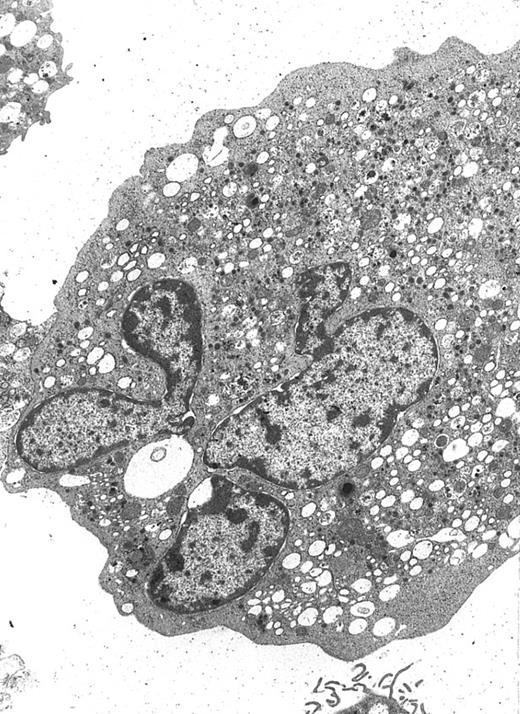

Electron microscopy.MP suspensions were fixed overnight with 2% glutaraldehyde in PBS at 4°C. A rinse in PBS of the specimen preceded the 1 hour of postfixation in 1% OsO4 in PBS at 4°C and wash in distilled water. On the same occasions, fixed MP were incubated with anti-CD61 antibodies (clone VPL2; kindly provided by W. Knapp, Wien, Austria) and with goat antimouse IgG conjugated with 15-nm colloidal gold particles (Jansen, Beerse, Belgium). Dehydration was performed using a graded ethanol series from 70% up to 100% and propylene oxide. After embedding in Araldite, ultrathin sections (silver or very pale gold) were obtained with a Reichert Jung ultramicrotome, counterstained with uranyl acetate and lead citrate, and observed with a CM10 transmission electron microscopy at 80 kV (Philips, Eindhoven, The Netherlands).

A well-differentiated megakaryocyte (original magnification × 3,080) generated from purified CD34+ cells cultured for 12 days in the presence of MIP-1α, IL-3, IL-6, IL-11, FL, SCF, and MGDF. A normal distribution of granules, mitochondria, and other cytoplasmic organelles is visible.